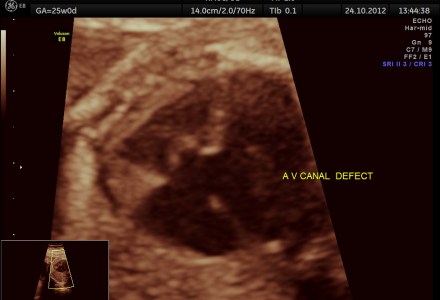

ENDOCARDIAL CUSHION DEFECT ( A.V.CANAL DEFECT OR A.V.SEPTAL DEFECT)